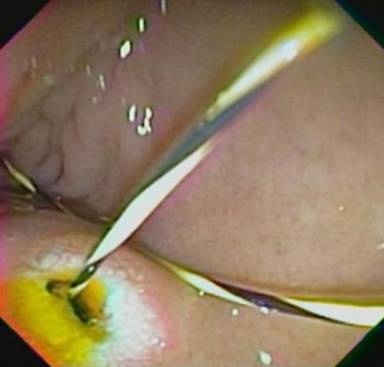

Upper endoscopy had previously shown duodenal stenosis due to circumferential ulcerated and infiltrative lesions in all cases. Facing a high probability of an unsuccessful ERCP, we discussed the possibility of endosonography-guided biliary drainage and duodenal stenting with the surgical and oncological teams. We performed the procedure following the same sequence in all cases. For the whole procedure, the patient was under general anesthesia and fluoroscopic guidance was used. A therapeutic duodenoscope (TJF-160, Olympus, Tokyo, Japan) was introduced and advanced until the duodenal bulb. A 0.035 guidewire (Jagwire®, Boston Scientific, Natick, MA, USA) was advanced through the duodenal stenosis until the proximal jejunum (Figure 1). The stenosis was dilated with a dilation balloon (CRETM Balloon Dilator, Boston Scientific, Natick, MA, USA) until 15 mm. The duodenoscope was advanced but the major ampulla could not be identified. The guidewire was left in place and the duodenoscope was removed. A linear array echoendoscope (GF UCT-140, Olympus, Tokyo, Japan; Alfa 5 processor, Aloka, Tokyo, Japan) was introduced. Endosonography examination was performed to look for the dilated common bile duct, the largest left intrahepatic duct and the presence of collateral veins. In all cases, the largest left intrahepatic ducts were smaller than 6 mm and we did not attempt the antegrade transhepatic access. The common bile duct was punctured with a 19-gauge needle (EUSN-19T, Cook Medical, Bloomington, IN, USA) (Figure 2). Bile was aspirated and contrast was injected to confirm an adequate position of the needle (Figure 3). After confirmation with fluoroscopy, a 0.035 guidewire (Jagwire®, Boston Scientific, Natick, MA, USA) was advanced through the needle into the common bile duct and the needle was retrieved. A 6-Fr cystotome (Endo Flex, Voerde, Germany) was then inserted over the guidewire to create a bilioenteric communication (Figure 4). In four patients, a partially covered biliary self-expandable metallic stent (WallFlex® 60/100 mm, Boston Scientific, Natick, MA, USA) was inserted into the common bile duct and successfully deployed, creating a choledochoduodenal fistula (Figure 5). In one patient (Patient#2), we deployed an uncovered biliary metallic stent (WallFlex® 60/100 mm, Boston Scientific, Natick, MA, USA). The echoendoscope was removed and the duodenoscope was introduced over the duodenal guidewire. A non-covered duodenal self-expandable metallic stent (WallFlex® 120/220 mm, Boston Scientific, Natick, MA, USA) was inserted over the guidewire and deployed in all patients (Figures 6 and 7).

Figure 4. Biliary and duodenal guide-wires. |